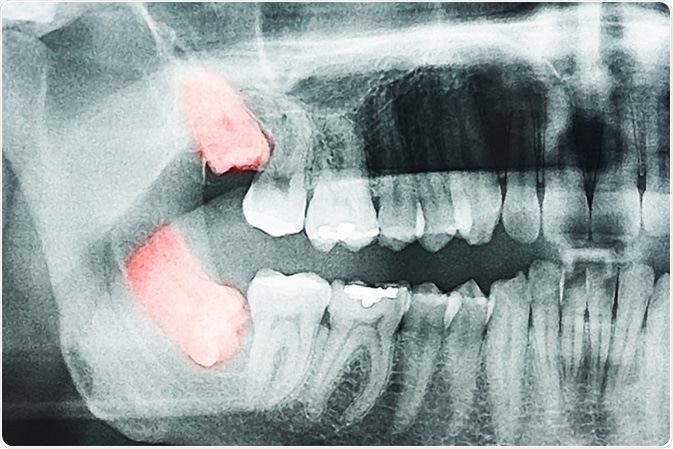

On the other hand, some individuals may have impacted or embedded wisdom teeth. This type of wisdom tooth has lost its capability to erupt in the mouth and remain lodged inside the jaw bone. It may require a surgical intervention for its removal.

Growing Wisdom Teeth Pain On X-Ray. Image Credit: Radu Bercan / Shutterstock